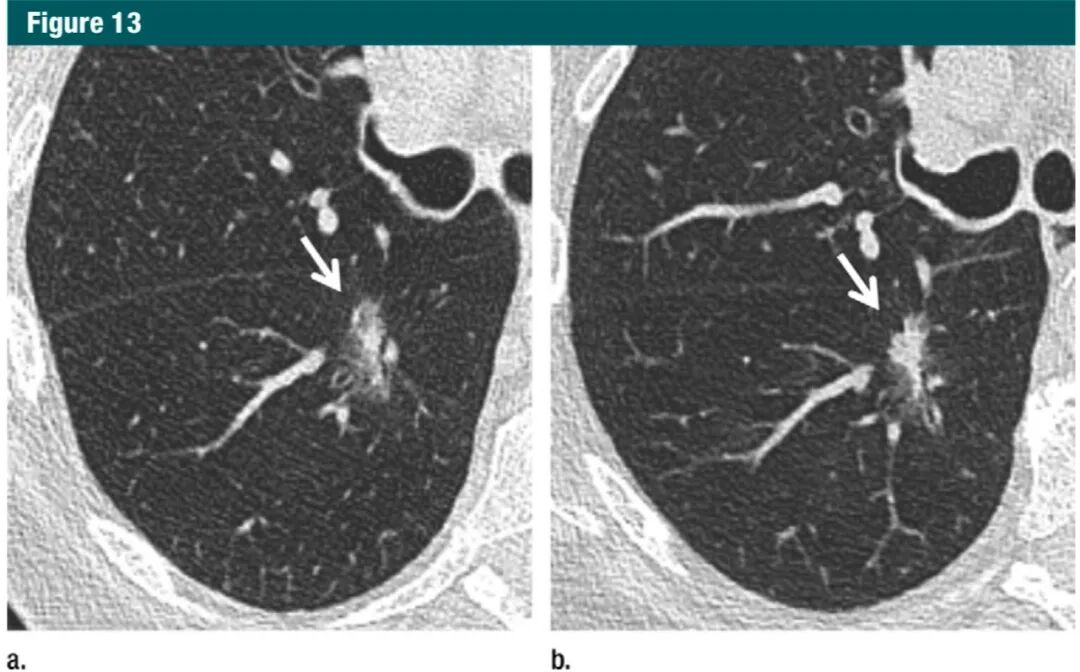

对于孤立性部分实性结节,实性成分≥6mm,应该考虑短期随访(3-6个月),以评估结节的是否仍存在。对于形态特别可疑的结节(如分叶、囊性成分)、实性成分增多、或者实性成分>8mm,建议 PET/CT,活检,或切除(1B级:强烈建议,中等质量证据)。大量研究证据显示,实性成分越多,浸润性和转移的风险越大。实性成分>5mm 很大可能性与局部侵袭有关。这是新修订的腺癌 T 分期中的临界值(图 13)。然而,短期的部分实性结节中也可以出现大量实性成分。

图片7Gc帝国网站管理系统

图13:a.横断位1mmCT,显示右肺下叶背段一个高度可疑的部分实性结节(病灶大,磨玻璃样和实性形态);b.3个月后随访显示实性部分明显增多;术后病理为浸润性腺癌。7Gc帝国网站管理系统